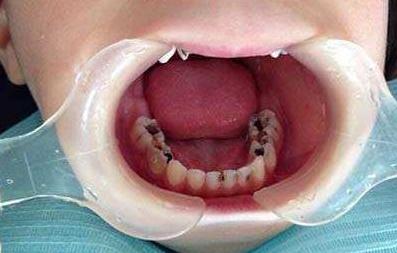

三、小孩牙齿坏了不需要治疗

这种说法是有一定前提的,很多老人之间都流传着小孩子牙齿不用治疗等他自己换就行的一种说法。这种说法其实是不正确的,因为小孩子乳牙损坏程度过大是会影响到恒牙的生长的。